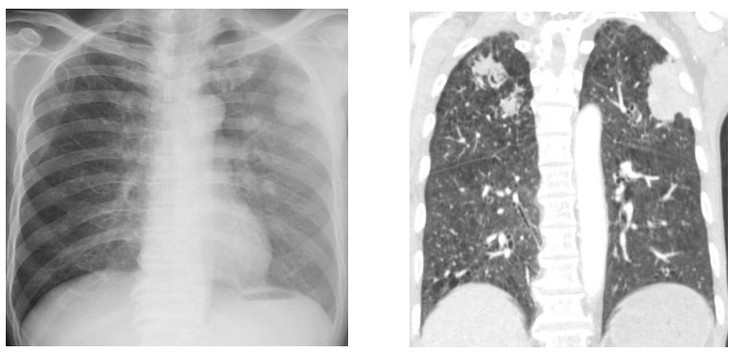

Tại khoa Hô hấp - Hồi sức tim mạch, kết quả chụp cắt lớp vi tính ngực và ổ bụng cho thấy hẹp môn vị nghi do ký sinh trùng và tổn thương phổi hoại tử hai bên. Xét nghiệm dịch rửa phế quản phát hiện ký sinh trùng, bệnh nhân được chẩn đoán nhiễm giun lươn nặng ở phổi và điều trị đặc hiệu theo phác đồ.

| Tổn thương phổi hoại tử hai bên của người bệnh. Ảnh BVCC |